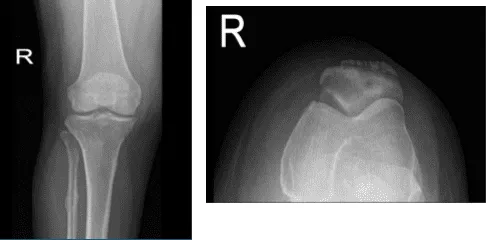

A 53 year-old female went to the office with her X-ray and complained of right knee pain for about weeks and she does not remember if it is from fall or injury, she has not gained weight, fever, chills. Upon the physical and X-ray examinations result, Sunrise patella, AP and lateral.

Distal femur, patella, proximal tibia and proximal fibula demonstrate intact cortical margins with no acute fracture. There is a suggestion for a healed fracture proximal shaft right fibula. There is mild narrowing of the medial joint compartment with slight osteophyte formation

There is spurring from the superior pole of patellar anteriorly. A joint effusion is present There is no radiographic evidence of soft tissue swelling. There are mild osteoarthritic degenerative changes. A joint effusion is present. There are no fractures.

Right knee X-ray AP and Lateral